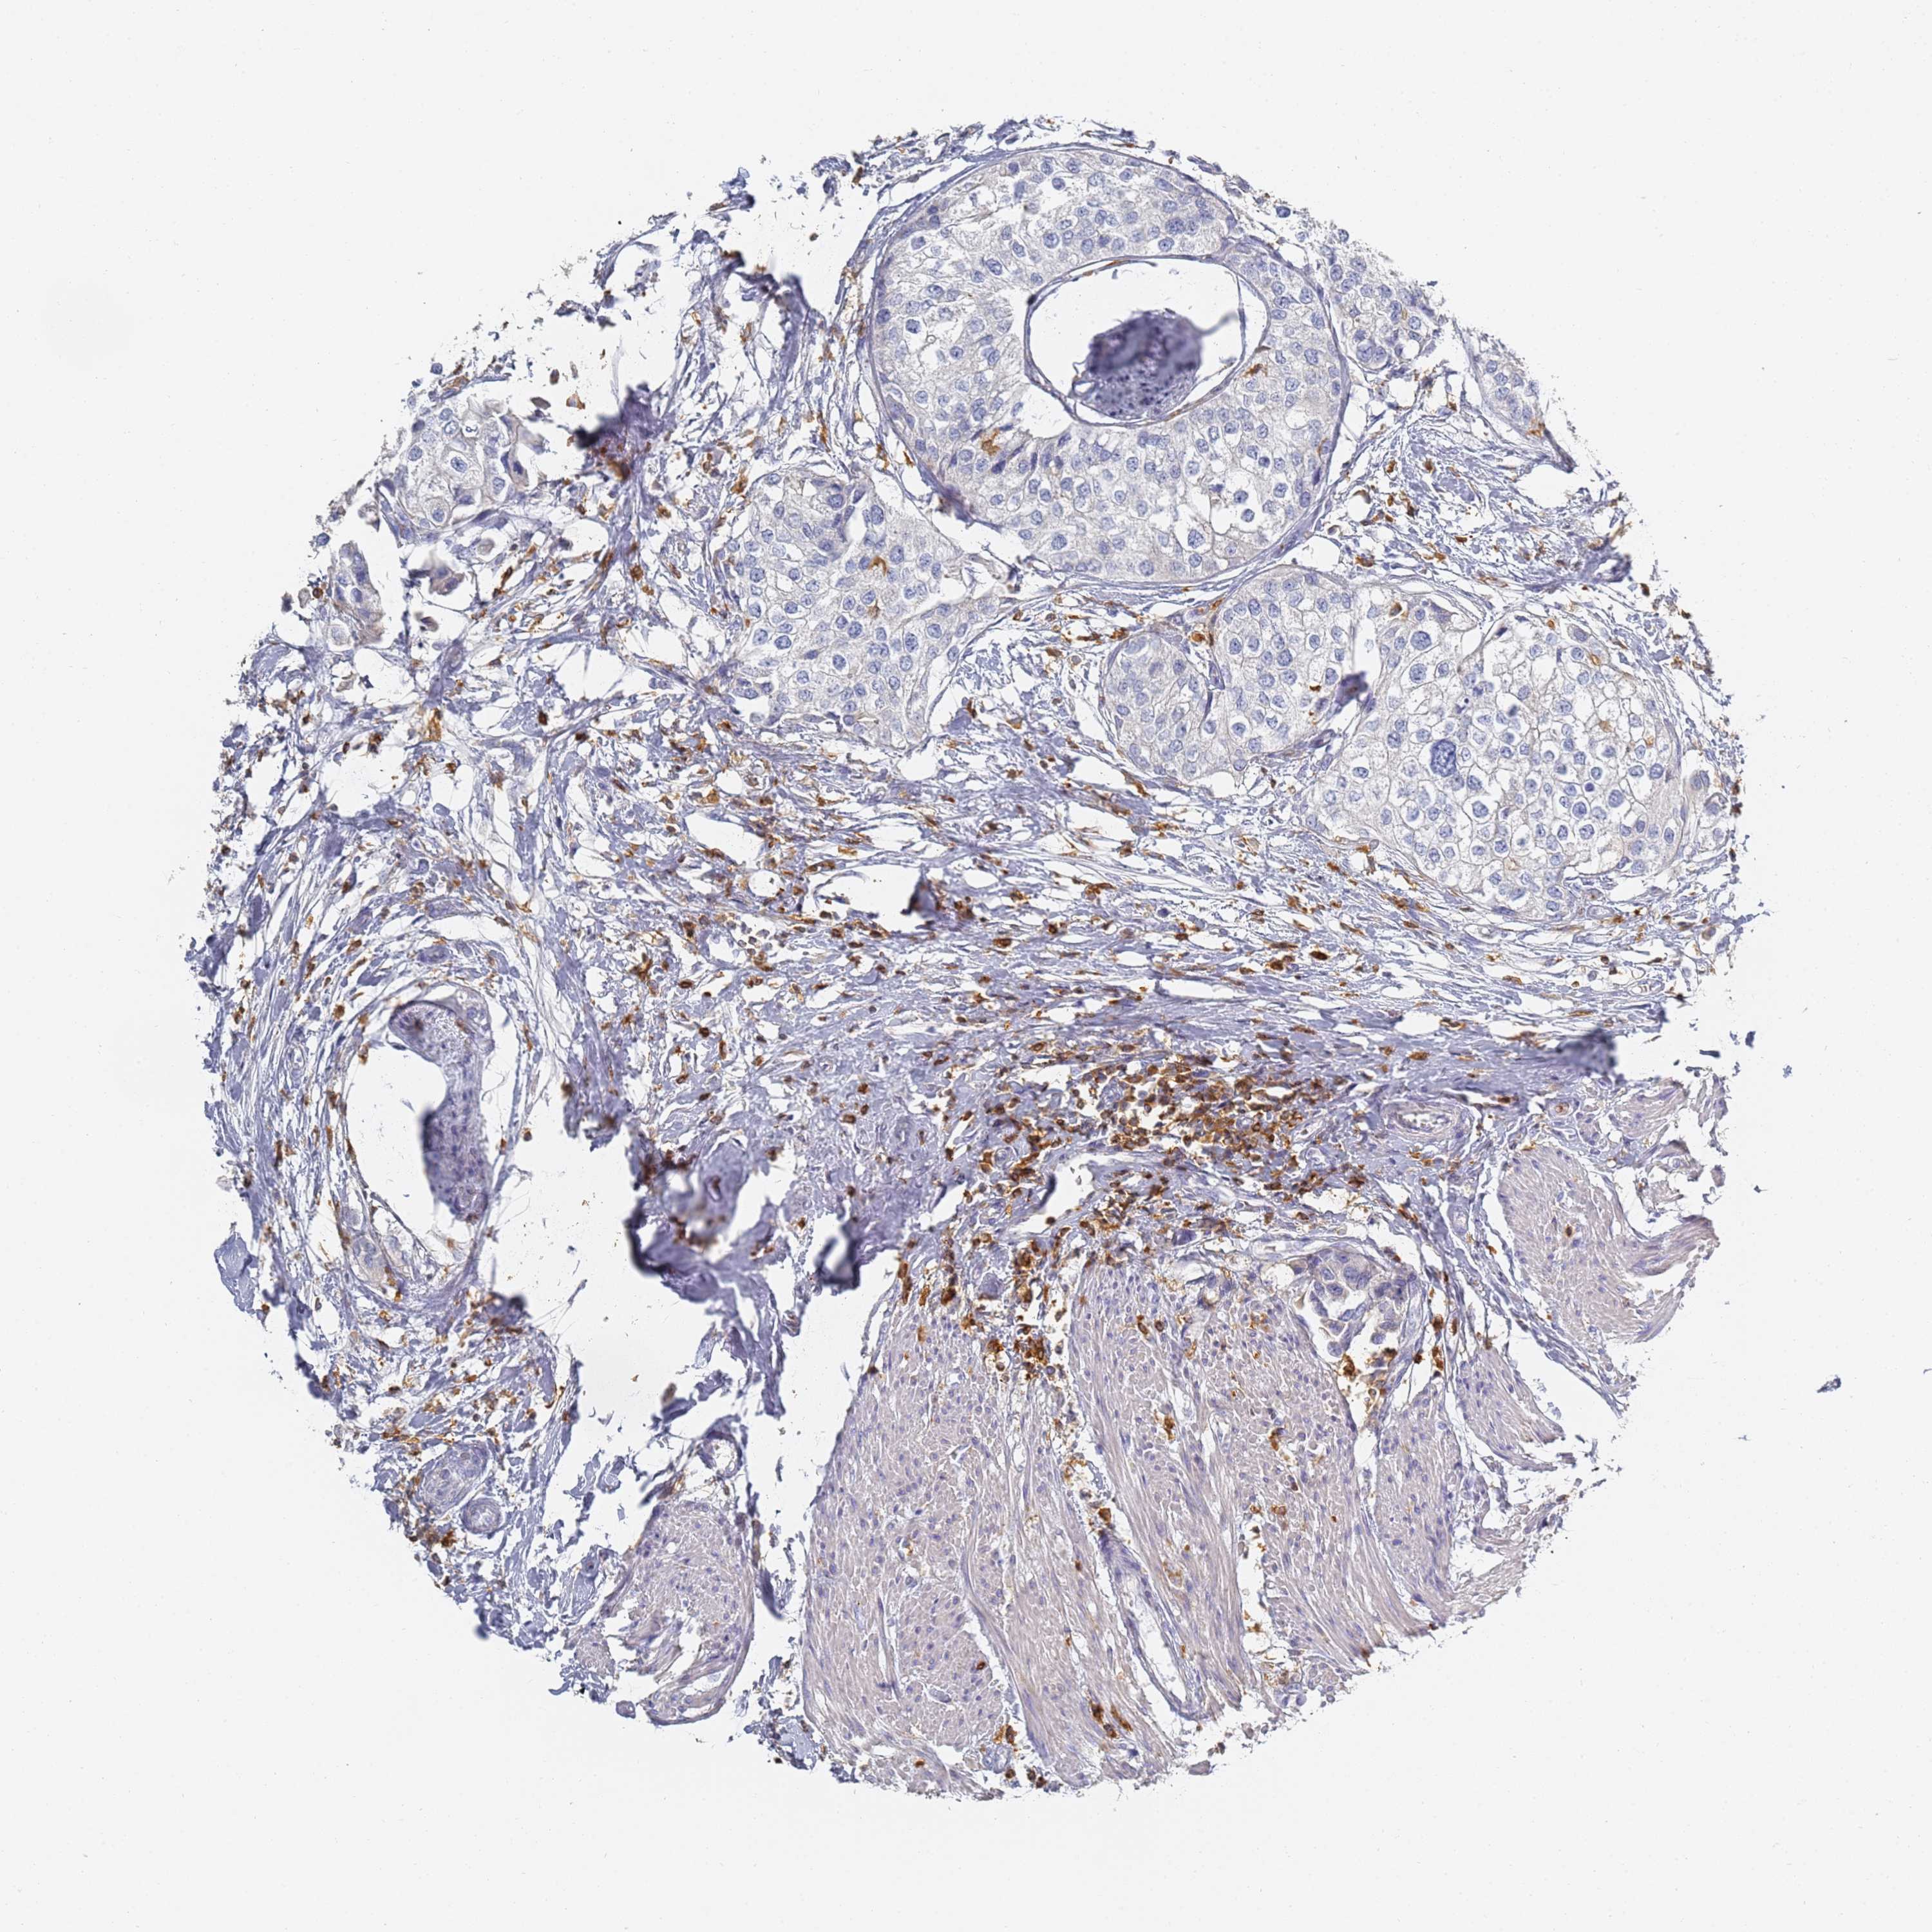

UROTHELIAL CANCER - Protein expressioni

A mouse-over function shows sample information and annotation data. Click on an image to view it in a full screen mode. Samples can be filtered based on level of antibody staining by selecting one or several of the following categories: high, medium, low and not detected. The assay and annotation is described here.

Note that samples used for immunohistochemistry by the Human Protein Atlas do not correspond to samples in the TCGA dataset.

Antibody stainingi

Antibody staining in the annotated cell types in the current human tissue is reported as not detected, low, medium, or high, based on conventional immunohistochemistry profiling in selected tissues. This score is based on the combination of the staining intensity and fraction of stained cells.

Each image is clickable and will lead to virtual microscopy that enables deeper exploration of all samples and also displays staining intensity scores, fraction scores and subcellular localization as well as patient and tissue information for each sample.

Antibody HPA038666

Antibody HPA038667

Urothelial carcinoma, High grade

Urothelial carcinoma, Low grade